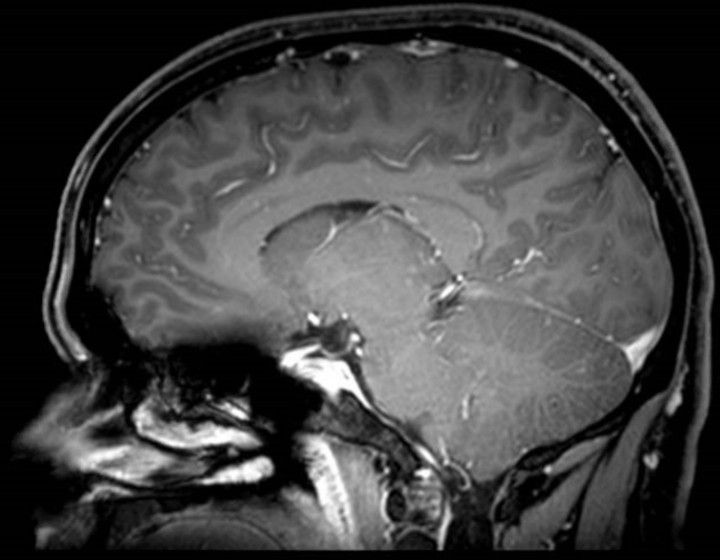

neurosurgery